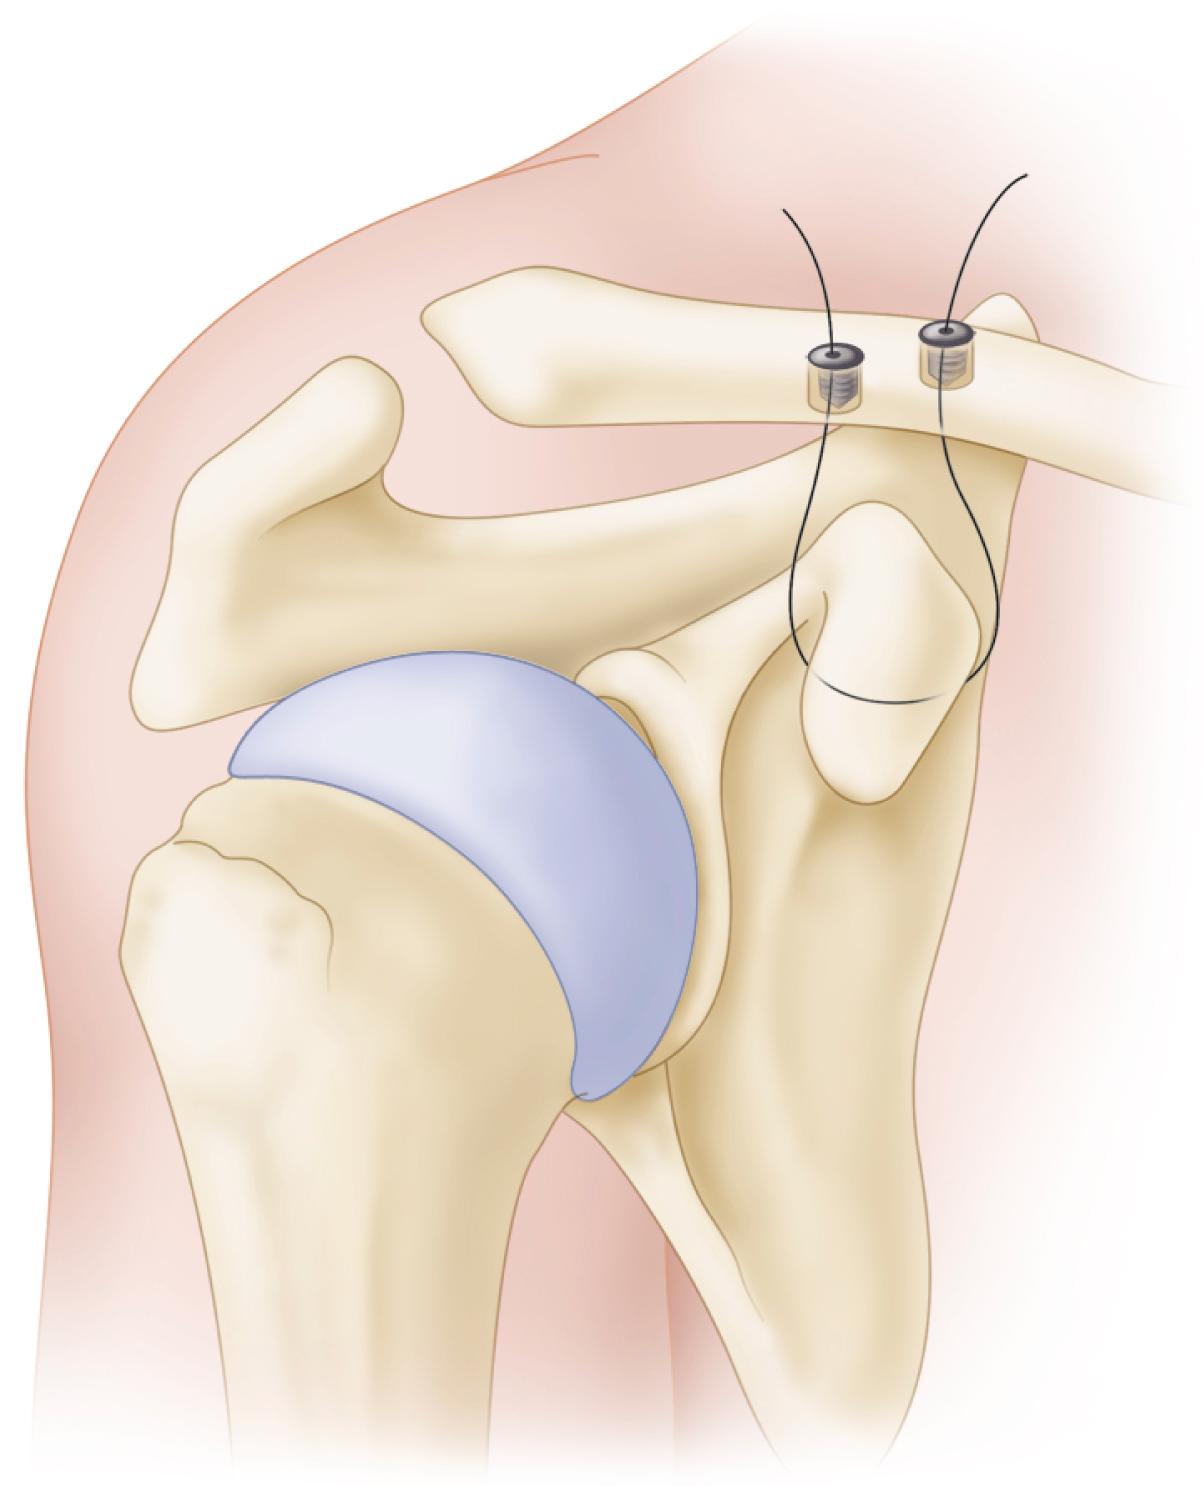

Neer described five types of lateral clavicular fractures ( Table 57.5 and Fig. 57.7 ). Types I and II are lateral to the coracoclavicular ligaments and are inherently stable. Type II fractures occur just medial to the coracoacromial ligaments (type IIa) or occur with rupture of the ligaments (type IIb). The trapezius can be a deforming force and cause displacement of type II fractures. Treatment is still controversial, with good results reported with both operative and nonoperative treatment, even with malunions. The challenge is to obtain secure fixation in the lateral segments. Anatomic locking plates have improved fixation in the distal segment ( Fig. 57.8 ) Other strategies include plating over to the acromion to gain greater fixation, supplementing fixation with sutures from the clavicle to the coracoid ( Fig. 57.9 ), and using subacromial hook-plates ( Figs. 57.10 and 57.11 ). High rates of union (95% or higher) and good shoulder function have been reported with the use of hook-plates, but patient discomfort and acromial osteolysis generally require plate removal as soon as union occurs. The author uses hook plates only in rare circumstances and recommends judicious use.

FIGURE 57.9, Supplemental suture fixation from clavicle to coracoid over the acromion for lateral clavicular fracture.

Recently, Yagnik et al. reported a combination of cortical button fixation with coracoclavicular ligament reconstruction for distal clavicular fracture repair. Fractures united in all patients with low complication rates ( Fig. 57.12 ).

FIGURE 57.12, Distal clavicle repair using combination of cortical button fixation and coracoclavicular ligament reconstruction.